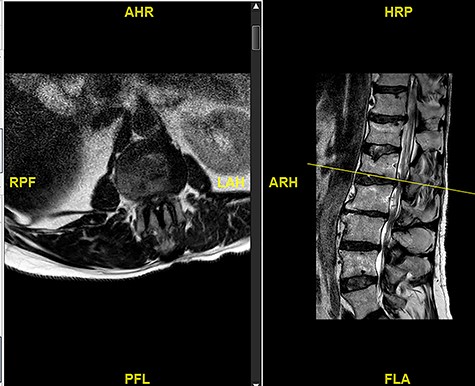

The updated MRI scan showed large disc prolapse at L4/5 level (Fig. 4) and the patient underwent emergency laminectomy/discectomy at L4/5. Post-operatively the patient’s pain improved however there still a retained loss of perineal sensation to pin-prick, a urinary catheter tug awareness was present and a good lower limb power was documented. The patient was discharged on the third post-operative day having been successfully mobilized and decatheterized with spontanous micturition.

The patient represented just over a month following the surgery to report about new onset weakness in the plantar flexion bilaterally, urinary incontinence, persistence of perineal sensation loss and new erection problems. There was no report of any pain and ambulation was still at ease. An MRI scan was organized a few days later (Fig. 5). The finding was deemed to be an IDH. Therefore, revision surgery followed the next day, with a durotomy and extraction of intradural disc fragments. As the patient had sphincter disturbance with neurogenic bladder and bowel difficulties, a referral to the regional spinal injury unit for aftercare as well as to the sexual dysfunction clinic for erection problems were organised.